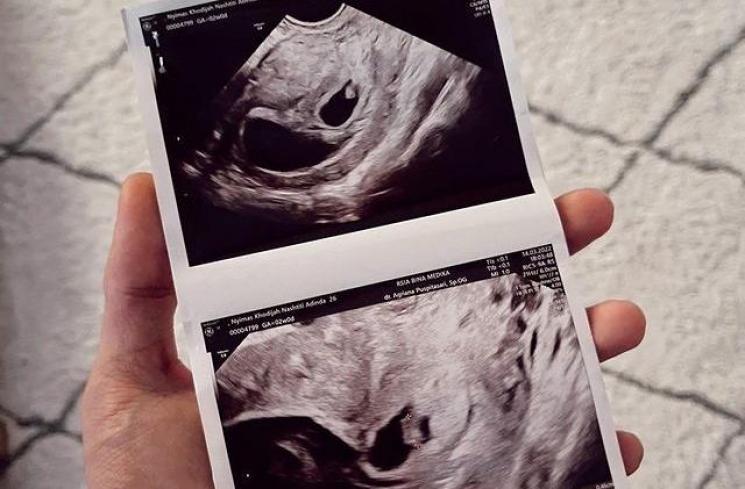

Segera setelah tiba di tanah air, Dinda dan Rey Mbayang melakukan cek USG untuk memeriksa kehamilannya. Dokter mengungkapkan bahwa kehamilan Dinda Hauw kali ini adalah anak kembar. Dinda dan Rey pun bahagia atas kabar dari dokter itu.

3. Satu Janinnya Tidak Berkembang

Di balik kabar bahagia atas kehamilan kembarnya, Dinda Hauw harus menelan pil pahit saat tahu bahwa salah satu janinnya tidak berkembang dan satu kantung rahimnya kosong.